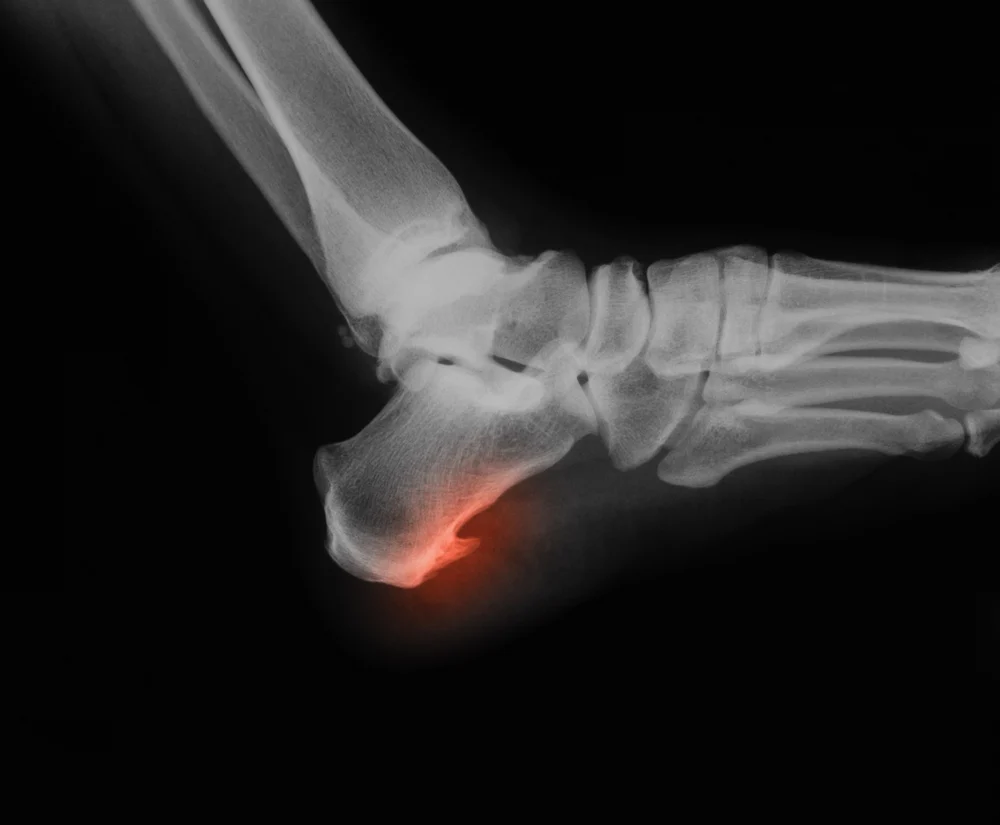

مهدی رحمانی در تن سالم ۱ ماه پیش - خواندن ۵ دقیقه خار پاشنه: وقتی گام های زندگی دوباره لذت بخش می شوند آیا تا به حال تجربه ی درد تیز و سوزاننده ای را در پاشنه پای خود داشته...